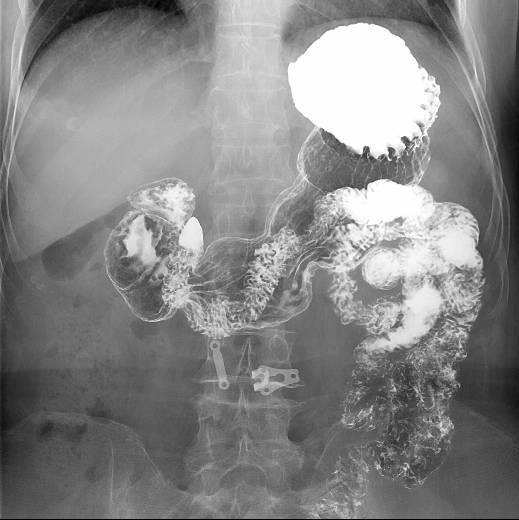

食道长轴、胃全景、胃小沟与胃小区局部放大精细数字图像、下消化道全景等;

胃肠造影

肠道气钡双重造影